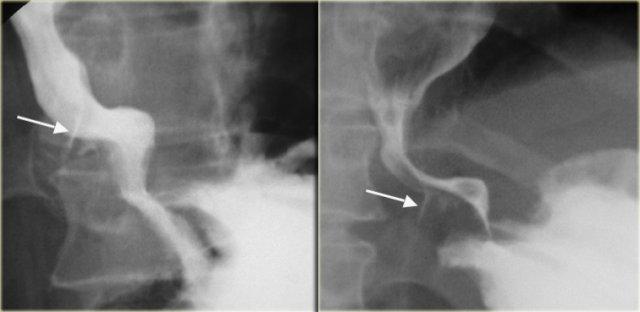

Bên trái là hình ảnh một bệnh nhân bị rách niêm mạc Mallory-Weiss.

Phim chụp điểm cho thấy barium (các mũi tên) trong vết rách niêm mạc dạng tuyến tính gần chỗ nối thực quản – dạ dày.

Vết rách có thể ở thực quản đoạn xa, đáy vị hoặc kéo dài qua chỗ nối thực quản – dạ dày.